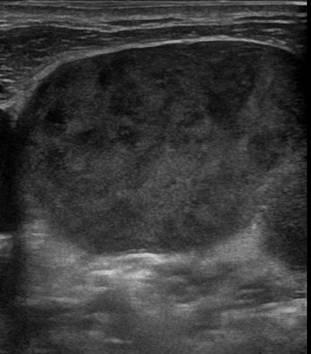

УЗИ лимфоузлов при лимфоме Ходжкина

Раздел: Образы вокруг